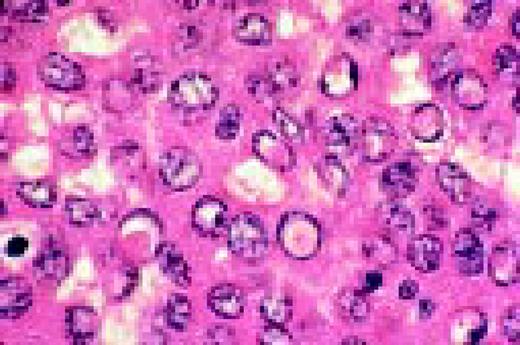

Slide L42

IgA myeloma, bone marrow biopsy. Several of the plasma cells contain intranuclear inclusions referred to a Dutcher bodies. These structures are found in a wide spectrum of immunoproliferative disorders and had been most frequently associated with plasmcytoid lymphomas. They lack specificity for any subtype of the immunoproliferative processes.FIG42